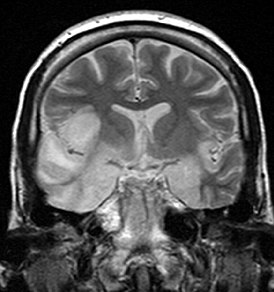

Ветряной энцефалит: Это редкое осложнение ветрянки, которое может возникнуть при вирусной инфекции головного мозга. Ветряной энцефалит может привести к серьезным последствиям, включая нарушение мозговой деятельности, паралич и даже смерть. В осложненных случаях может потребоваться госпитализация и интенсивное лечение.